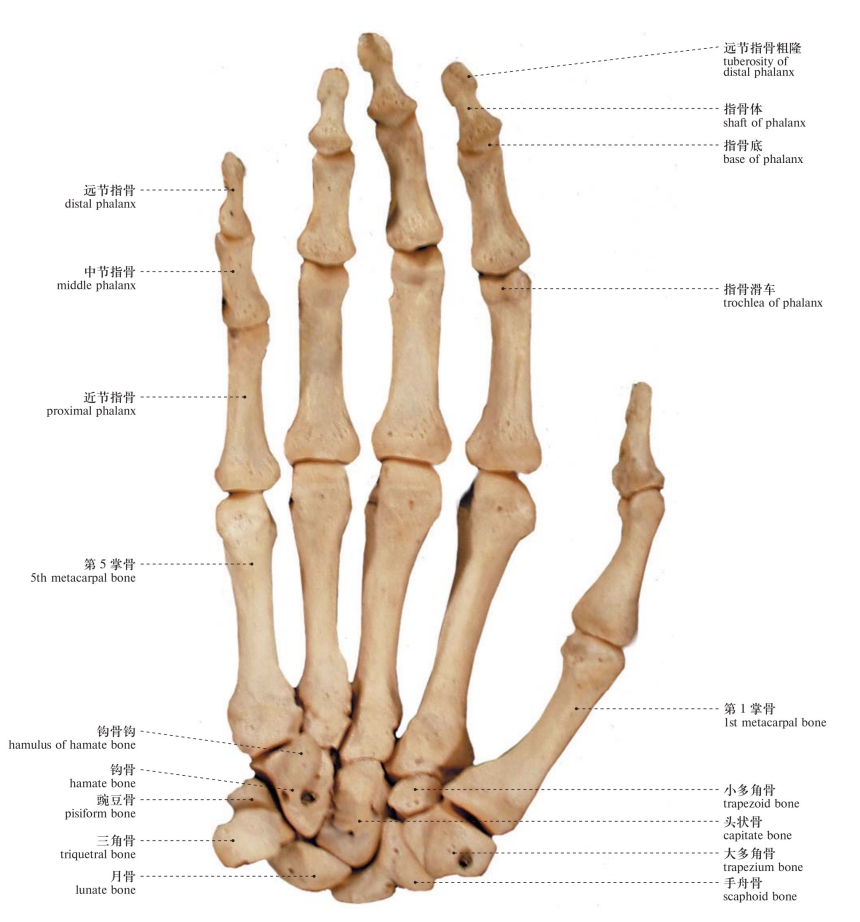

图98 手骨(掌面观)

Bones of the hand (palmar aspect)